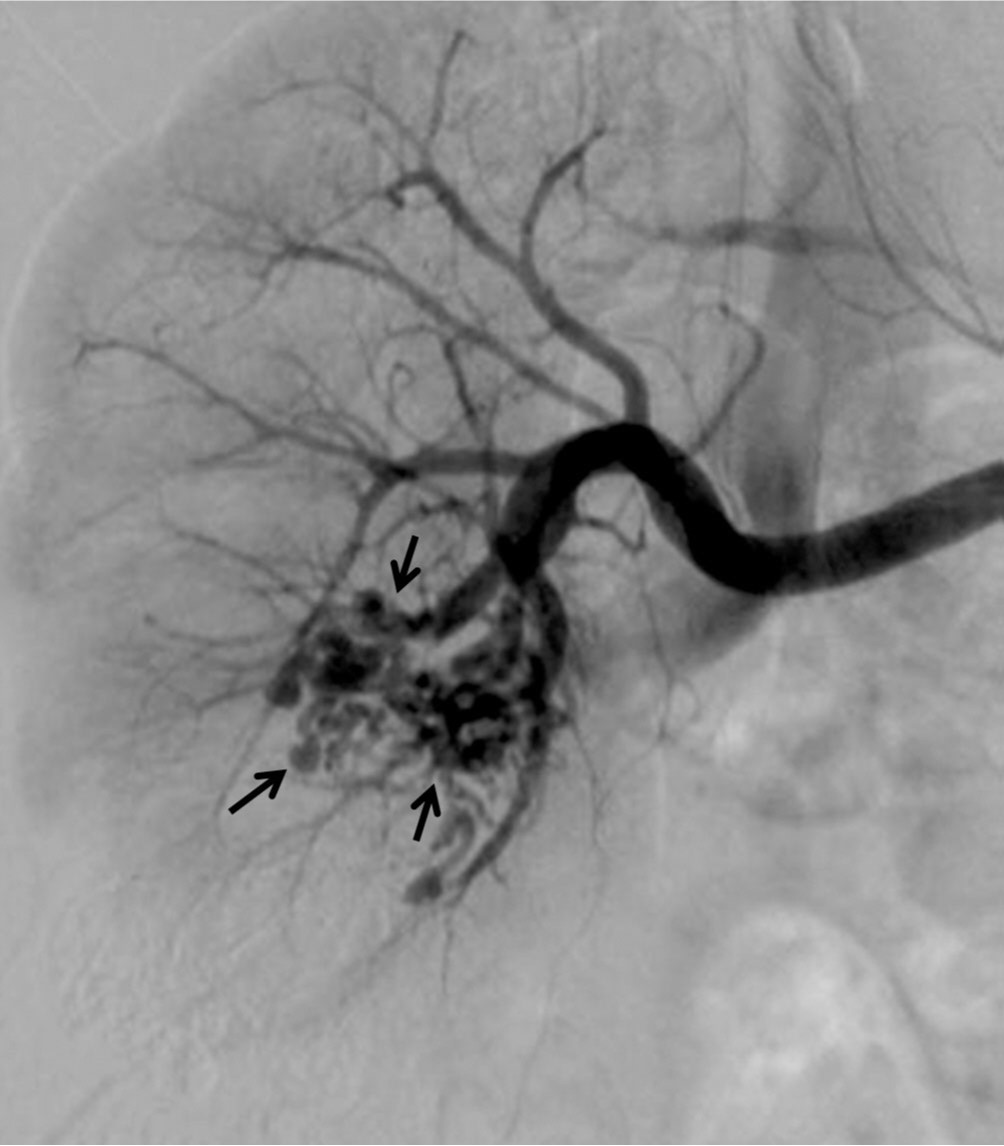

Fig. 2.

Fig. 2. Right renal arteriogram shows a network of tangled hypervascular structures (arrows) with early venous drainage.